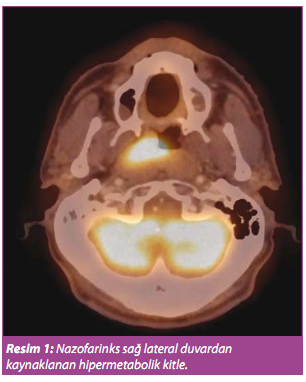

Bu bölge ile ilgili larinks kanseri dışında nazofarinks (Resim 1), orofarinks, özefagus gibi diğer tüm bölgelerin primer tümörlerinde evreleme, yeniden evreleme ve tedaviye yanıt amaçlı kullanılabilir. Larinks kanserinde de PET/BT özellikle kitleye eşlik eden lenf bezlerinin karakterizasyonu ve metastatik odak varlığının araştırılması için kullanılabilir ama devlet ödeme endikasyonları içinde yeralmamaktadır.